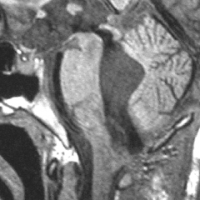

左小脳にできた小さな のう胞性血管芽腫です。矢印の先にある小さな塊だけが腫瘍で周囲は腫瘍から染み出した液体が溜まっています(のう胞といいます)。右側は血管撮影とMRIを組み合わせた画像で,腫瘍に動脈が流入しているのが見えます。